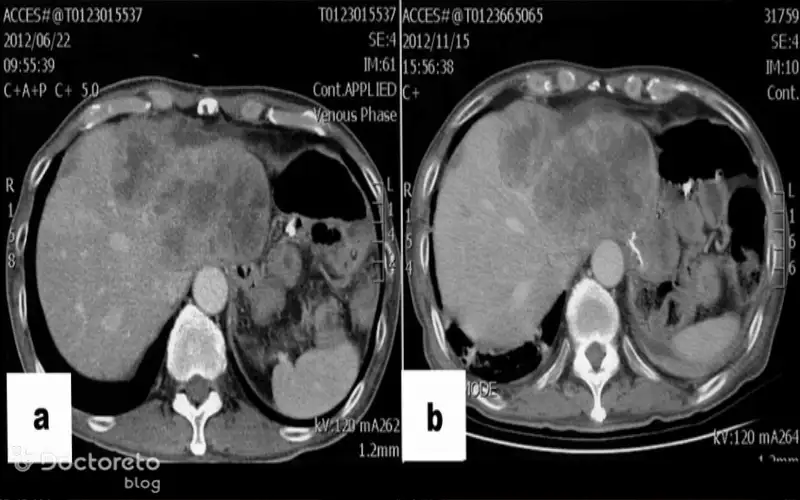

عکس سرطان معده بدخیم در مراحل پیشرفته

در این بخش، تصویری از سرطان معده بدخیم در مراحل پیشرفته را نشان دادهایم. در چنین شرایطی تومور علاوه بر معده، ارگانهای مجاور مانند کبد، ریه و استخوان یا اندامهای دیگر را هم درگیر کرده است. در این مرحله، درمان چالشبرانگیزتر شده و پیشبینی روند بیماری دشوارتر است.